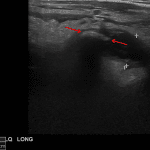

- Appendix is distended measuring up to 13 mm in diameter with mural thickening, periappendiceal edema, and a 12 mm appendicolith

Acute appendicitis

Appendix is distended measuring up to 13 mm in diameter with mural thickening, periappendiceal edema, and a 12 mm appendicolith, concerning for acute appendicitis.

No discrete adjacent fluid collection to suggest abscess.